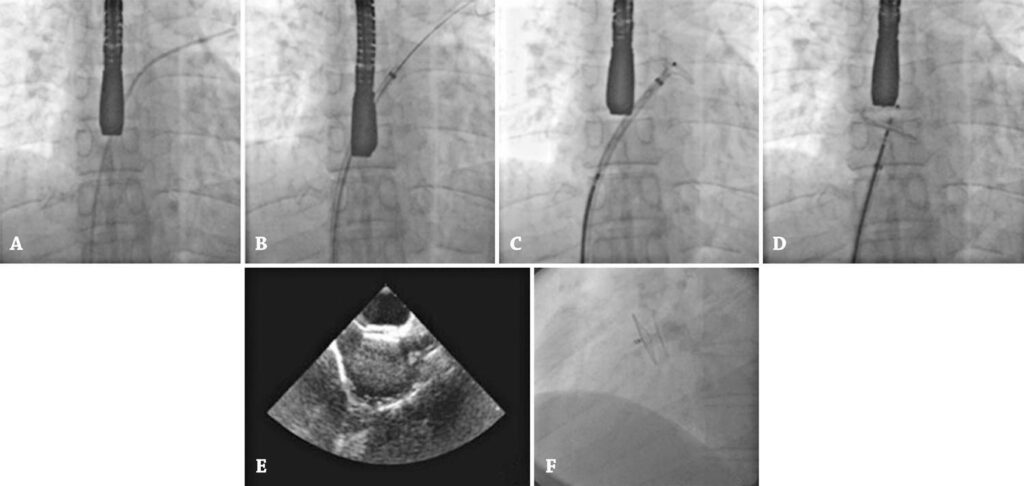

Left-to-right shunting via the foramen ovale is a potential cause of paradoxical embolism. The presence of patent foramen ovale in more than 40% of patients with idiopathic ischemic stroke has led to deeper investigation of the impact of its closure on decreasing stroke recurrence rates. This study describes 20 years of experience with percutaneous patent foramen ovale occlusion performed by a single operator.

This sample comprised 527 patients with ischemic stroke submitted to percutaneous occlusion of patent foramen ovale associated to left-to-right shunting.

The procedure was successful in all cases. The mean age was 48 years (range of 9 to 72 years), and 57% were male. Amplatzer® and Occlutech® prostheses were implanted in 295 and 232 patients (56% and 44%, respectively). There were no deaths, and complications were as follows: hematoma at the puncture site (three patients, 0.6%), femoral arteriovenous fistula with spontaneous resolution (two patients, 0.4%), cardiac tamponade resolved after puncture and drainage (two patients, 0.4%), transient supraventricular arrhythmia (22 patients, 4.2%), headache (27 patients, 5.1%), atrial fibrillation (two patients, 0.4%), large residual shunt requiring a second prosthesis (two patients, 0.4%), recurrence of ischemic stroke within 5 years (four patients, 0.8%) and hypersensitivity to nickel (one patient, 0.2%).